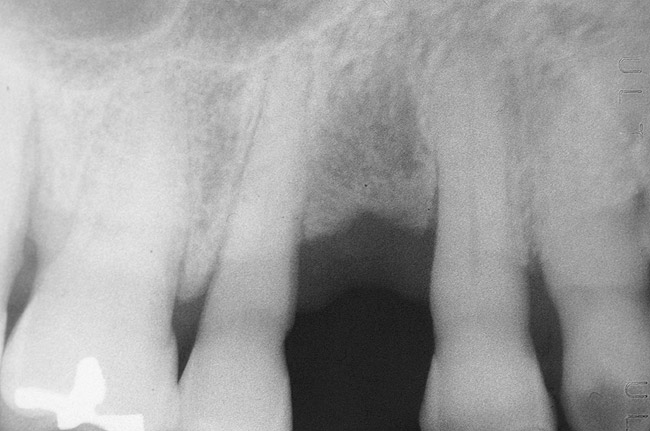

To meet the needs of the new paradigm, treatment techniques have evolved for bone preservation. Figure 1 shows a case in which tooth No. 5 had advanced bone loss and the treatment option was to save it. The patient did not opt to have this treated, however. Figure 2 shows the same area approximately 18 months later when the advanced bone loss was also affecting the adjacent teeth. Traditional treatment—extraction of this tooth—would have led to a significant hard- and soft-tissue defect. Use of the alternative treatment—grafting of the socket at the time of extraction19,20—preserved the hard and soft tissue (Figure 3 and Figure 4). Grafting the socket to minimize postextraction ridge shrinkage is a much more conservative approach than performing ridge augmentation after extraction,21 which would have been required if the socket grafting had not been done in conjunction with the extraction.

Figure 1  Tooth No. 5 showing advanced periodontal bone loss and a widened periodontal ligament space.

Figure 1

Figure 2  Same case as in Figure 1 after 1.5 years with no treatment. At that time, the bone loss affected the adjacent teeth. The apical extent of the bone loss was approximately 5 mm from the sinus floor.

Figure 2